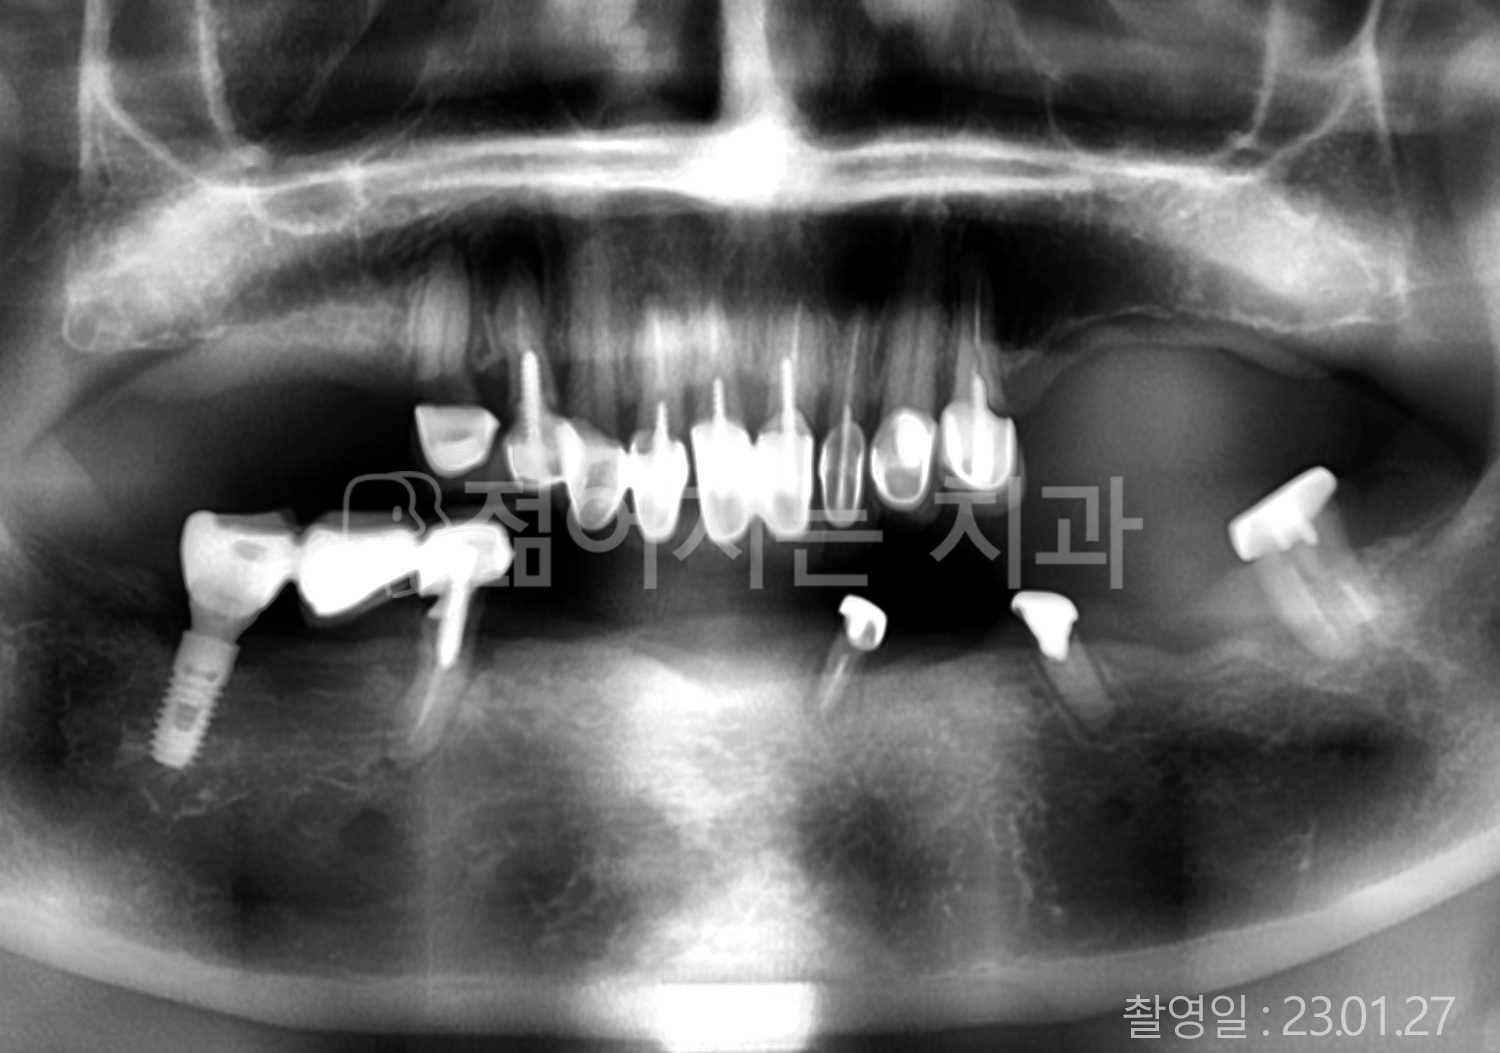

• 70대 고혈압, 고지혈증 전체치아 10개 이상 임플란트

• 60대 당뇨, 간염 전체치아 10개 이상 임플란트

• 80대 골다골증 전체치아 6개 이상 임플란트

• 70대 고혈압, 당뇨 전체치아 10개 이상 임플란트

• 60대 간 질환 전체치아 10개 이상 임플란트

• 60대 전체치아 10개 이상 임플란트

• 70대 전체치아 10개 이상 임플란트

• 50대 전체치아 10개 이상 임플란트

• 60대 고혈압, 고지혈증 전체치아 10개 이상 임플란트

• 40대 고지혈증, 뇌혈관 질환 전체치아 10개 이상 임플란트